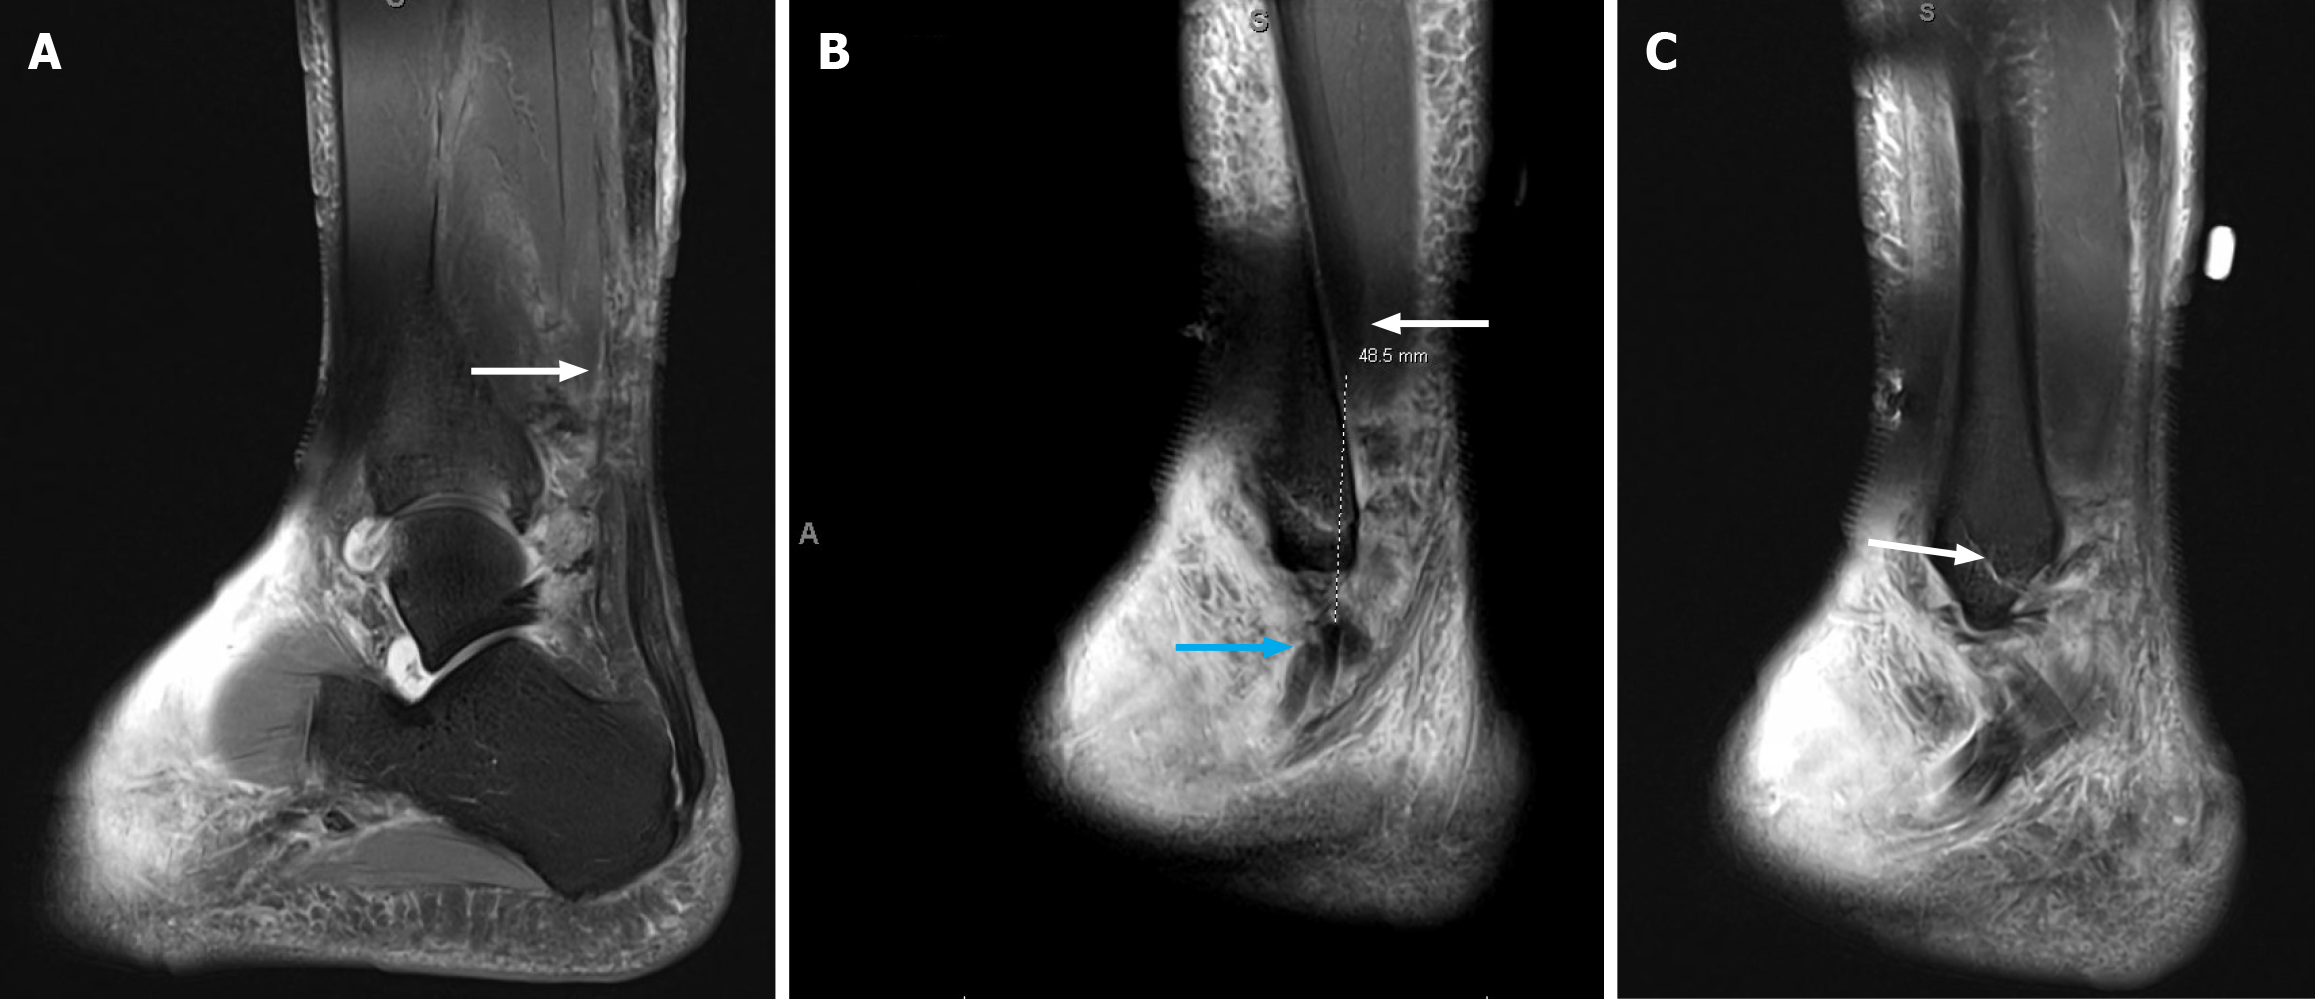

Figure 1 Sagittal spin-echo short inversion time inversion-recovery sequence magnetic resonance imaging of the ankle.

A: Image demonstrating mid substance Achilles rupture and adjacent soft tissue edema. White arrow indicates location of Achilles rupture; B: Image showing complete tears of the peroneus longus and brevis tendons, located just proximal to the lateral malleolus with approximately 5 cm of diastases between the tendon ends. Blue arrow demonstrates distal tendon stumps and white arrow demonstrates proximal tendon substance; C: Image of nondisplaced oblique distal fracture of the fibula. White arrow denotes the fracture.